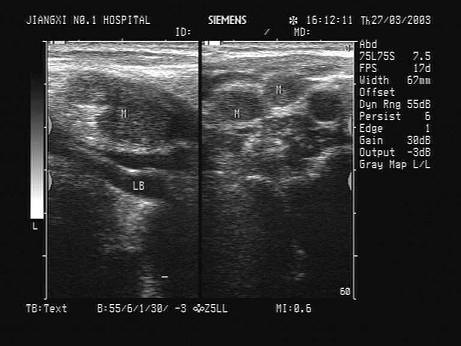

问题 患者发现颈部肿块两年余,无明显不适。甲状腺超声显示甲状腺及血管旁异常光团,如图。最可能的诊断为?(?)

选项 A.甲状腺癌 B.结节性甲状腺肿 C.甲状腺炎 D.甲状腺腺瘤 E.以上均不是

答案 A